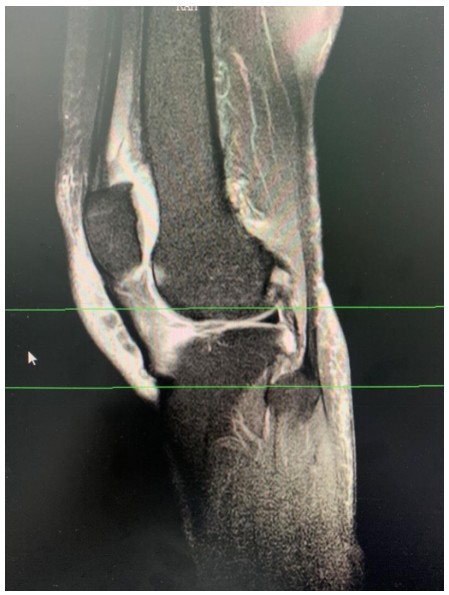

近日,衡陽市中心醫(yī)院華新院區(qū)疼痛門診接診了兩位年齡相仿、癥狀相似的女性患者,兩人都因一側膝關節(jié)腫脹、變形,疼痛難忍、下蹲受限、步行困難嚴重影響生活前來求診。兩位患者分別經(jīng)過張娟、趙夢岑兩位主治醫(yī)生的診治后被診斷為膝關節(jié)退變,并且發(fā)現(xiàn)患膝側關節(jié)內(nèi)存在大量積液。

膝關節(jié)炎是一種以退行性病理改變?yōu)榛A的疾患,好發(fā)于中老年人群,其癥狀多表現(xiàn)為膝關節(jié)腫痛、坐起立行時膝部酸痛不適等,偶有腫脹、彈響、積液等表現(xiàn)。如不及時治療則會導致關節(jié)畸形或殘疾。專家提醒,患有膝關節(jié)炎請及時到正規(guī)醫(yī)院就醫(yī),切莫因拖延耽誤了治療時機。